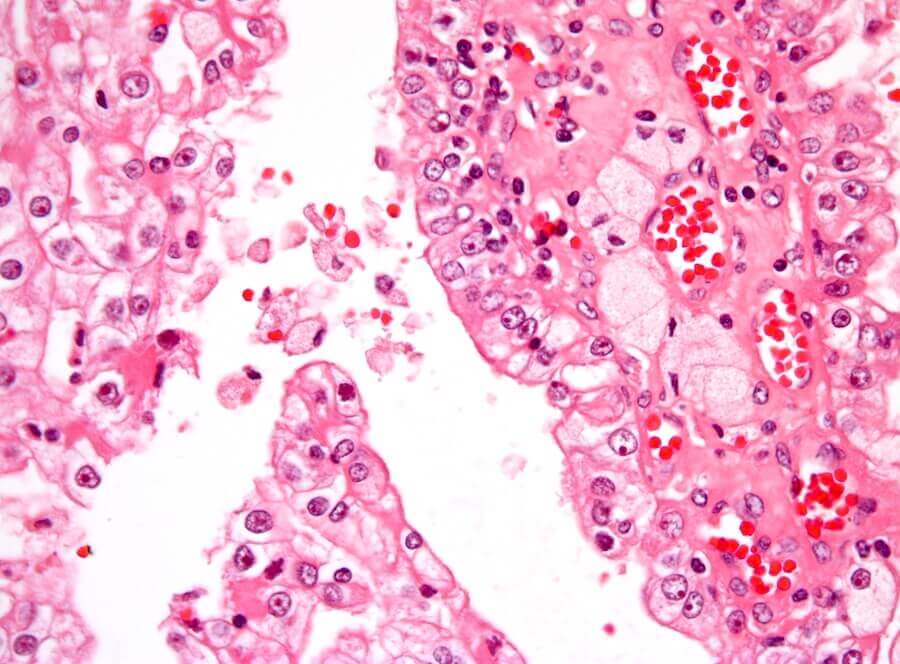

Selon les indications du spécialiste, on pourra réaliser une biopsie tumorale. Cela consiste à percer avec une aiguille pour prélever des cellules ou des tissus, en vue de leur analyse microscopique par un pathologiste.